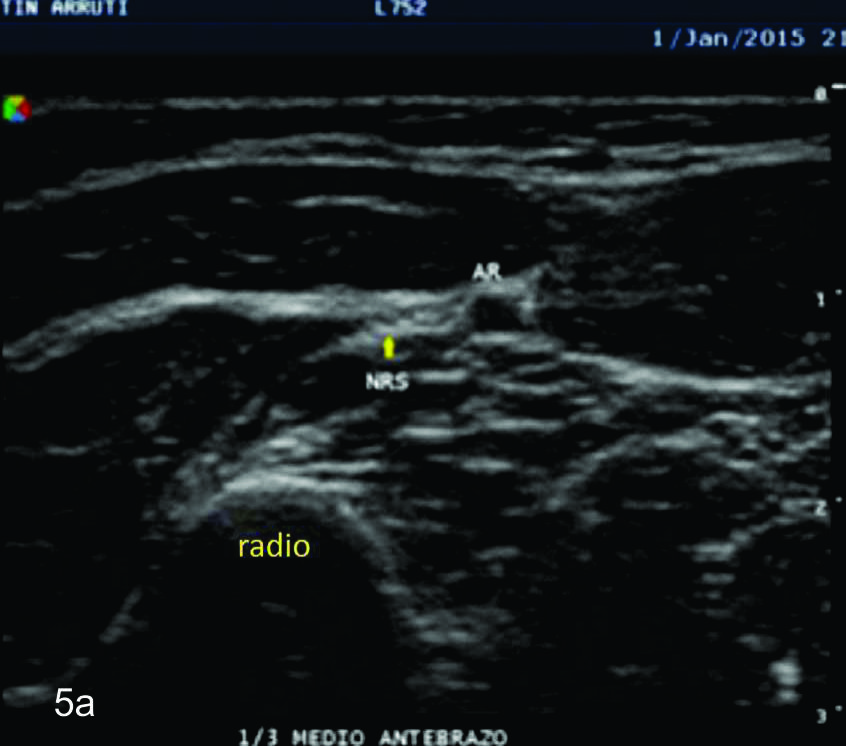

Figura 5

Nervio radial superficial

Cortes axiales del nervio radial superficial, desde su origen a nivel del codo como rama terminal del nervio cubital hasta la zona distal visible con el equipamiento empleado en tercio distal del antebrazo. Se identifica el mismo señalado por flechas amarillas, localizado adyacente a la arteria radial (AR).